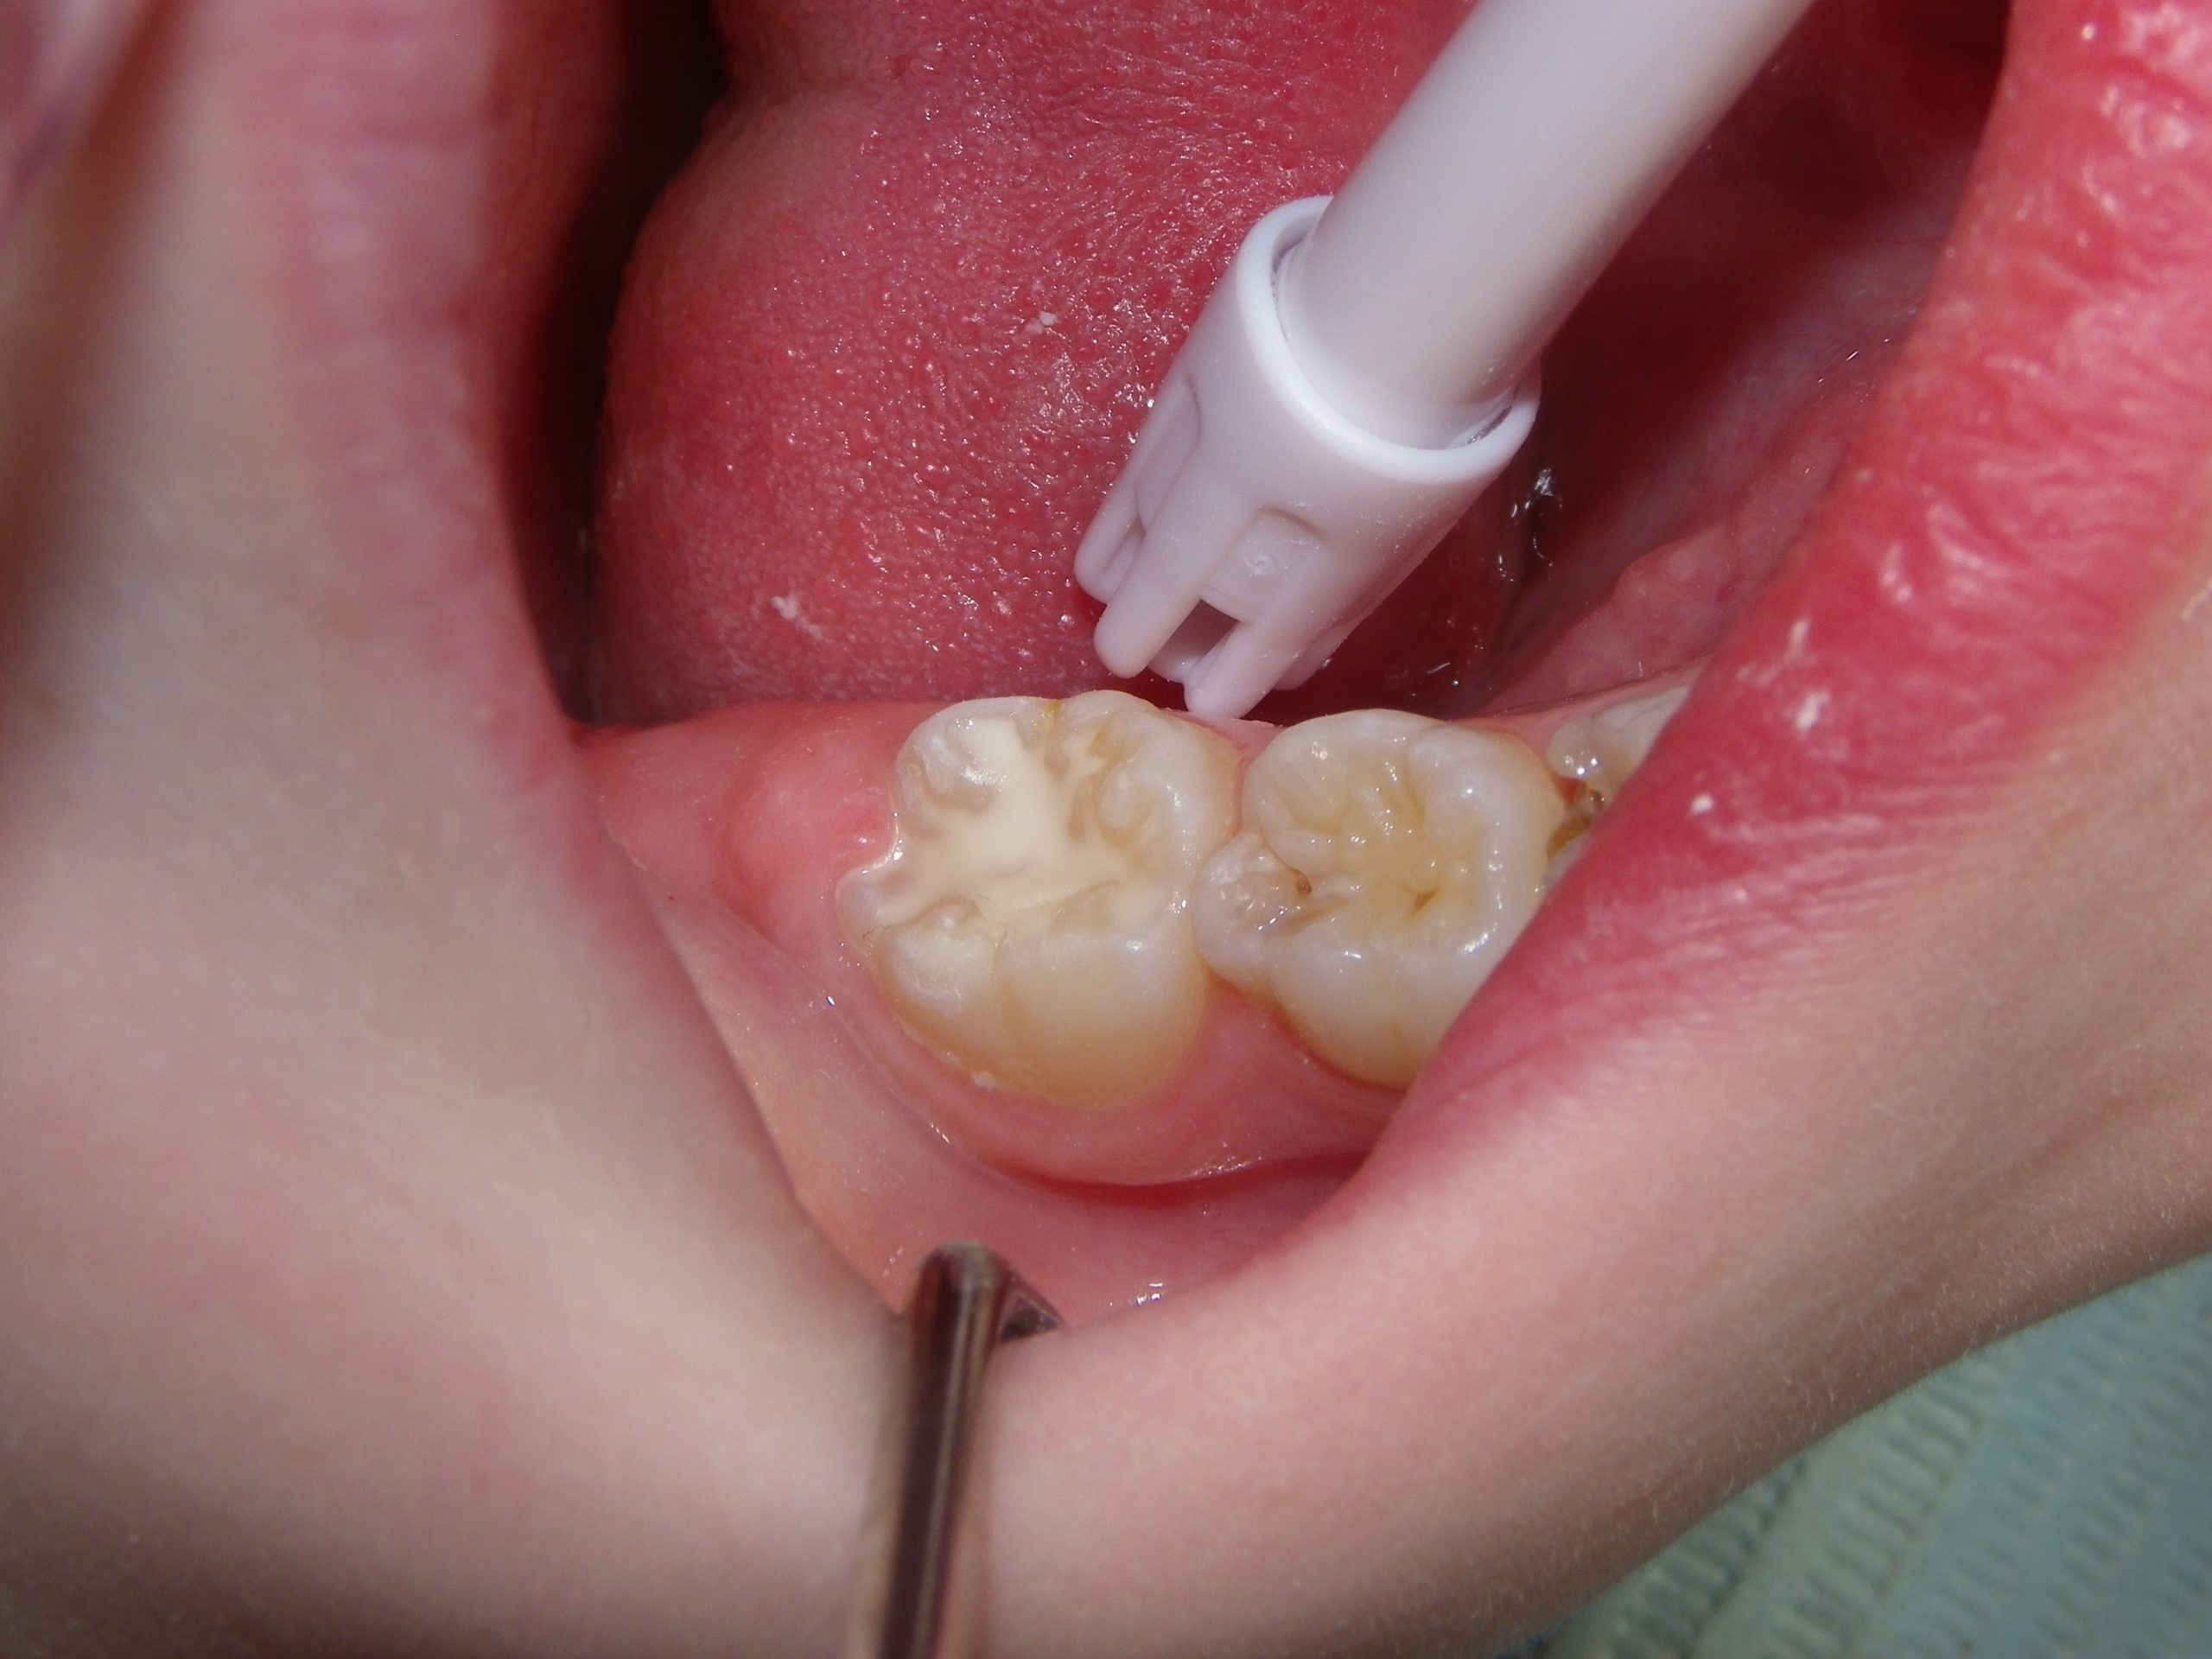

This quick photo series shows the step-by-step process of placing a sealant onto the grooves of an adult molar of a six-year-old. First, air abrasion is used to mechanically remove any loose surface debris or contaminants. Secondly, an acid gel is applied to the surface to be sealed. Finally, a sealant is applied to the surface and allowed to set. For the sharp-eyed, the sealant used was GC Fuji Triage, a glass ionomer sealant that while not as wear-resistant as the more commonly used resin sealants, is more moisture-friendly (ie: contamination resistant) and releases fluoride. The fluoride release allows the underlying enamel to be strengthened over time, making it more decay-resistant for the future.